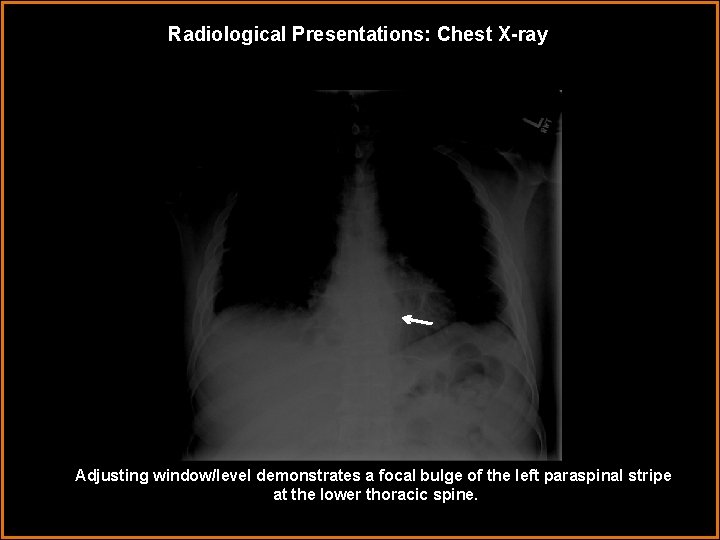

Radiological Presentations: Chest X-ray Adjusting window/level demonstrates a focal bulge of the left paraspinal stripe at the lower thoracic spine.

Findings and Differentials Findings: Chest radiograph demonstrates small bilateral pleural effusions with possible intervertebral disc space narrowing and illdefined endplates at one of the levels in the lower thoracic spine. A focal bulge at the lower left para spinal stripe is also visualized which is subtle. CT demonstrates T 8 -9 opposing endplate irregularity and erosive changes with mild pre- and paravertebral soft tissue swelling. MRI findings reveal altered marrow signal with enhancement of T 8 -T 9 vertebrae. Differentials: • Degenerative changes • Osteomyelitis • Vertebral body neoplasm